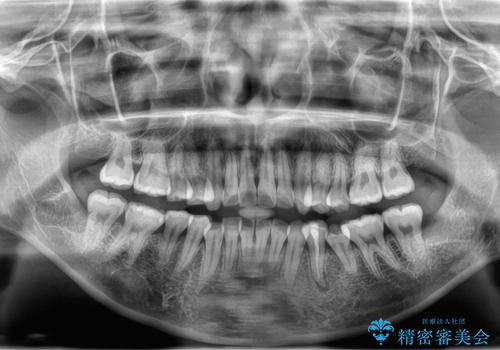

親知らず抜歯

- 親知らずを抜きたいとのことで来院。CTで神経の位置などを確認し、抜歯を行いました。1週間後には抜糸に来院予定です。

しっかり麻酔が効いていることを確認し抜歯を行いました。

親知らずがあると清掃性が悪くなるため手前の歯の虫歯のリスクが上がるので抜歯をおすすめします。